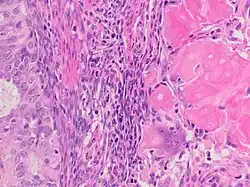

A ghost cell is an enlarged eosinophilic epithelial cell with eosinophilic cytoplasm but without a nucleus. It has lost its nucleus and cytoplasmic contents, leaving behind only the cell membrane and sometimes remnants of the cell's structure. In pathology, ghost cells are often associated with certain types of tumors, such as pilomatricomas and calcifying odontogenic cysts, where they appear as pale, anucleate cells that have undergone degeneration or calcification.

The ghost cells indicate coagulative necrosis where there is cell death but retainment of cellular architecture. In histologic sections ghost cells are those which appear as shadow cells. They are dead cells. For example, in peripheral blood smear preparations, the RBCs are lysed and appear as ghost cells.